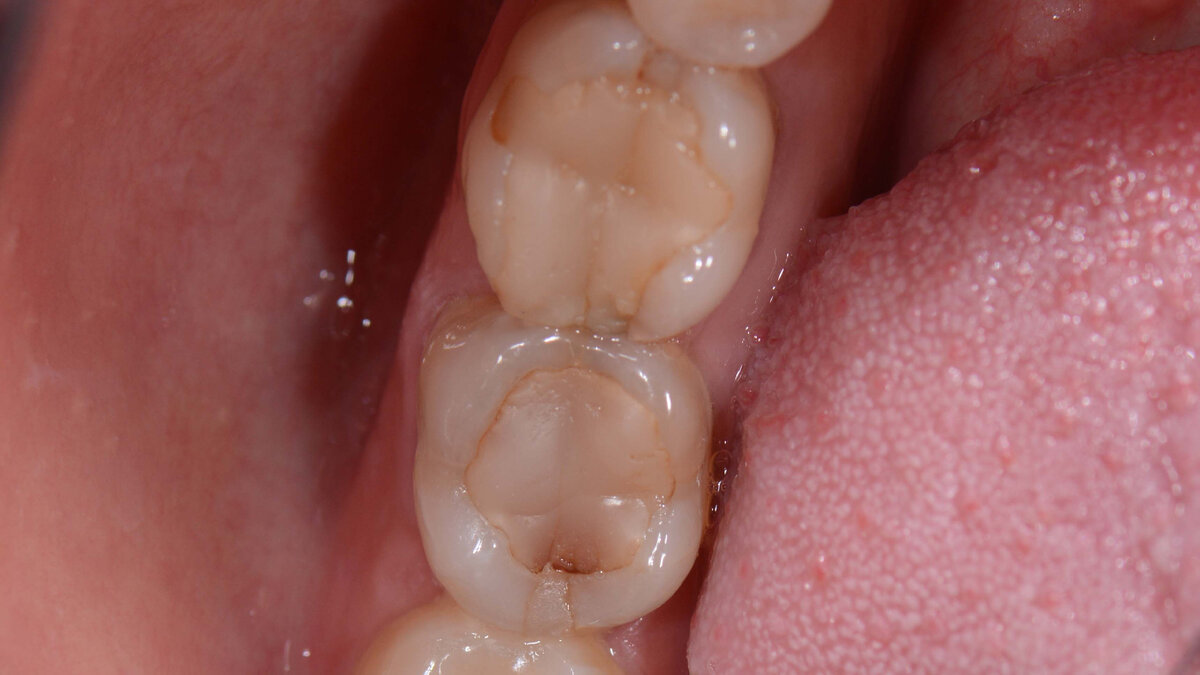

Стоматолог оценивает именно состоятельность пломбы, а не просто ее наличие в зубе. Если пломба проелась, стерлась, если нарушено краевое прилегание, если пломба имеет нависающий край и вредит десне, если есть кариес по границе пломба-зуб, то эта пломба подлежит замене, потому что зуб не жует как надо и незаметно разрушается. Особенно это касается депульпированных зубов (без нерва), потому что они никак не могут просигнализировать о наличии проблемы.

И для наглядности фото несостоятельных пломб: